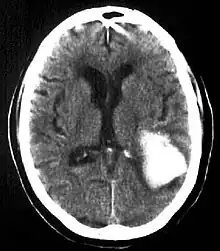

| Multiple intraparenchymal hemorrhage | |

Intraparenchymal hemorrhage is one form of intracerebral bleeding in which there is bleeding within brain parenchyma. The other form is intraventricular hemorrhage).[1]